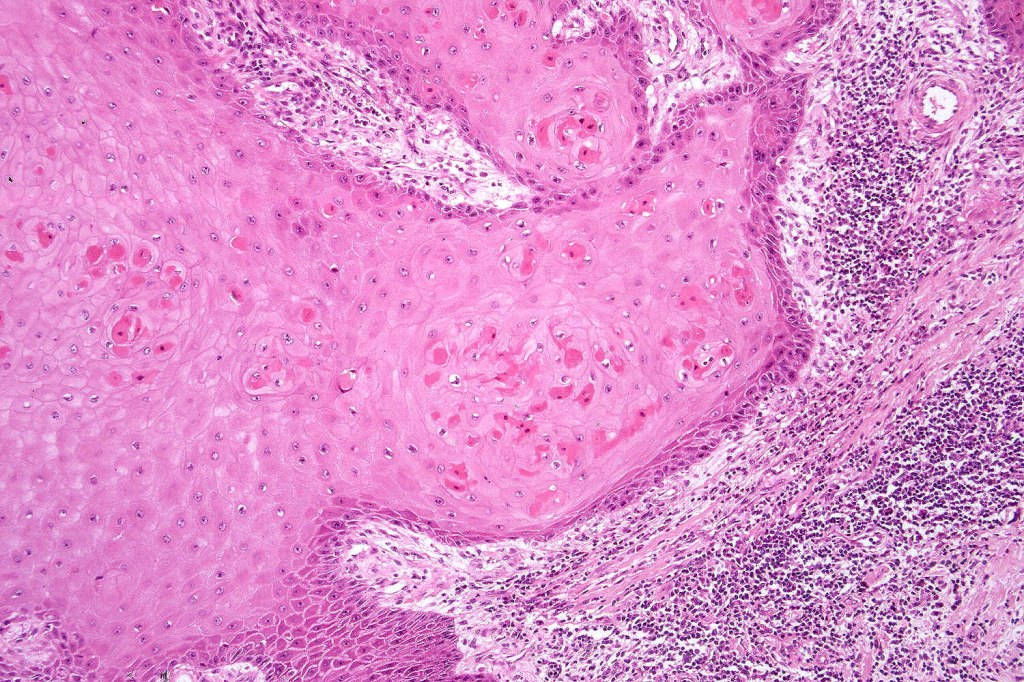

•Keratoacathoma (nowdays regarded as a variant of well differentiated squamous carcinoma) is characterized by a crateriform squamous epithelial lesion (dilated follicular infundibulum) with central keratin plug and adjacent collarette extending to the mid-dermis

•Well differentiated squamous epithelium often with a characteristic ground-glass appearance

•Only mild pleomorphism & basally located mitoses

•Neutrophil-rich microabscesses & necrosis

•Entrapped elastic fibers undergoing transepidermal elimination

•With evolution, the epithelium flattens with underlying fibrosis and chronic inflammation including a foreign body giant cell reaction to keratin